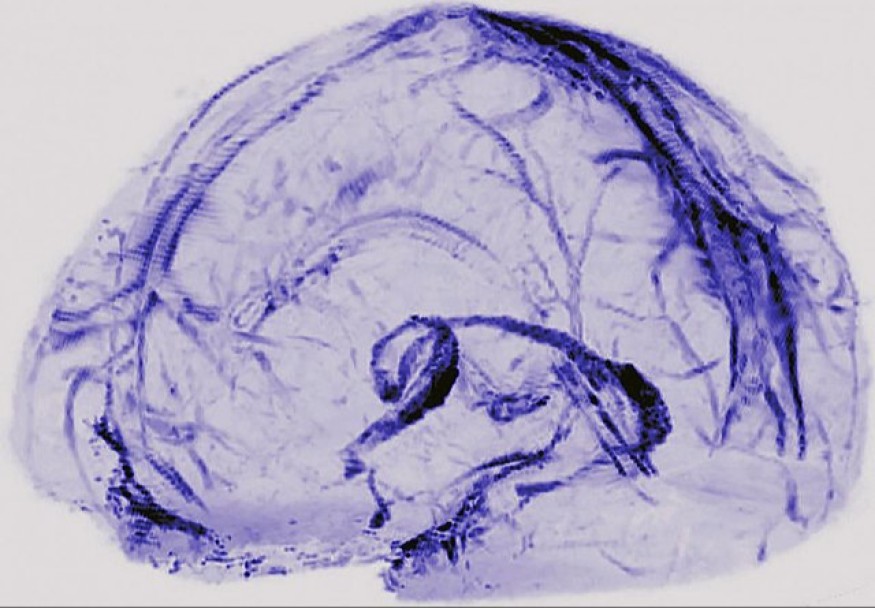

- Est-ce que le SARS-CoV2 persiste dans le cerveau ?